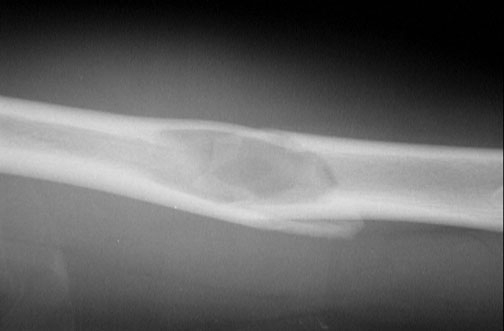

A fracture extends across a lucent area in this radiograph of the humerus. The area of lucency represents a unicameral bone cyst. The cyst weakened the bone so that a pathologic fracture occurred.